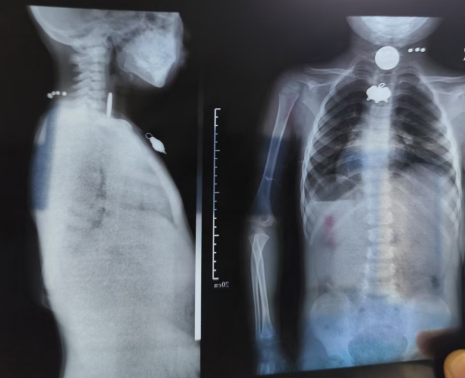

12月16日,虞城县人民医院内镜中心经历了一场分秒必争的“食管拆弹”行动。一名4岁男童在玩耍时不慎吞下一枚游戏币,异物牢牢卡在食管,导致孩子呼吸窘迫、剧烈干呕,被家长紧急送医。

救治面临巨大挑战:患儿处于“饱胃”状态,麻醉风险极高。在麻醉科医师王鑫对患儿实施快而稳的全身麻醉下,内镜医师林晓与护理团队展开了紧密无间的操作配合。进镜、寻踪、定位——内镜迅速抵达食管狭窄处,硬币赫然在目。

“视野清晰,准备抓取。” 林晓医师发出指令。护士崔钦钦默契地递上合适的异物钳,并全程稳持镜身,为医生提供最稳定的操作平台。在林医师精巧的操控下,异物钳稳稳夹住硬币边缘,彭东丽护士长同时协调患儿体位,确保异物取出路径通畅。随着内镜缓缓退出,一枚完整的硬币被成功取出,孩子食管的梗阻瞬间解除,呼吸随之平稳。